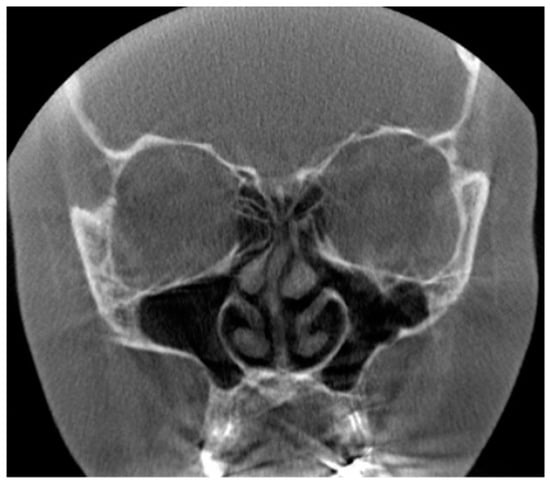

Figure 6. (Left): The coronal and sagittal CBCT slices present the signs of sinusitis and artifacts induced by dental restorations in the maxilla. Possible apical periodontitis cannot be distinguished accurately because of the artifacts. (Right): The coronal slice of CBCT image presenting mucosal thickening in the paranasal sinuses and artifacts induced by dental restorations hampering the evaluation of the periapical region of the teeth in detail.

The origin of the artifacts in the CBCT images is given in Figure 5. The main origins of the artifacts were large dental fillings or crowns in the upper jaw, being present in 203/214 (95%) of the CBCT images (Figure 6). Endodontic fillings of the maxillary teeth were the reason for artifacts in 111/214 (52%) of the images (Figure 7), followed by fixed dental prostheses and dental implants (Figure 8) causing the artifacts in 28/214 (13%) and 5/214 (2.3%) of the CBCT images, respectively. Other implants in the maxillofacial area were found only in three CBCT images, resulting in artifacts in levels 2 and 3 (Figure 3).

In re-evaluating the 214 CBCT images, we found that artifacts are common in elderly patients, as most of them have had restorative dentition treatments with a wide range of materials used. As an example, the CBCT image given in Figure 6 illustrates the detrimental effect of dental restorations. The magnitude of artifacts in CBCT images caused by materials used in dentistry depends on the atomic weight of the material as well as the size and thickness of the object [22]. According to the literature, titanium implants are the source of detrimental artifacts especially in the CBCT images [15,23,24], as are also the Zirconia implants [25,26,27]. Fiber-reinforced composites (FRC), which are clinically used in cranioplasty surgery, seem to be without detrimental effects in the CBCT images [28]. We have shown earlier that composite materials which consist of at least 20% radio-opacifying BaAlSiO2 fillers can cause artifacts in the CBCT images [29]. In the present study, there were only a few patients with dental (5/214) and maxillofacial implants (3/214), but as shown here, multiple dental implants cause deleterious artifacts (Figure 8).